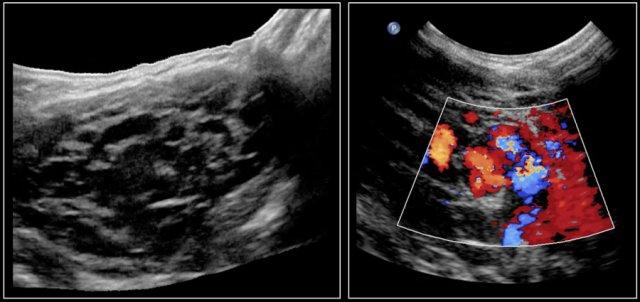

Trong bệnh Graves, tuyến giáp cũng to ra và cho thấy sự tăng tưới máu.

Trên siêu âm Doppler màu, hình ảnh này được mô tả như một địa ngục lửa với màu đỏ và xanh.

Đây là hình ảnh của một bé gái 16 tuổi mắc cường giáp.

Tuyến giáp to lan tỏa với tình trạng sung huyết.

Chẩn đoán cuối cùng là bệnh Graves.

Bệnh nhân được điều trị bằng I-131.